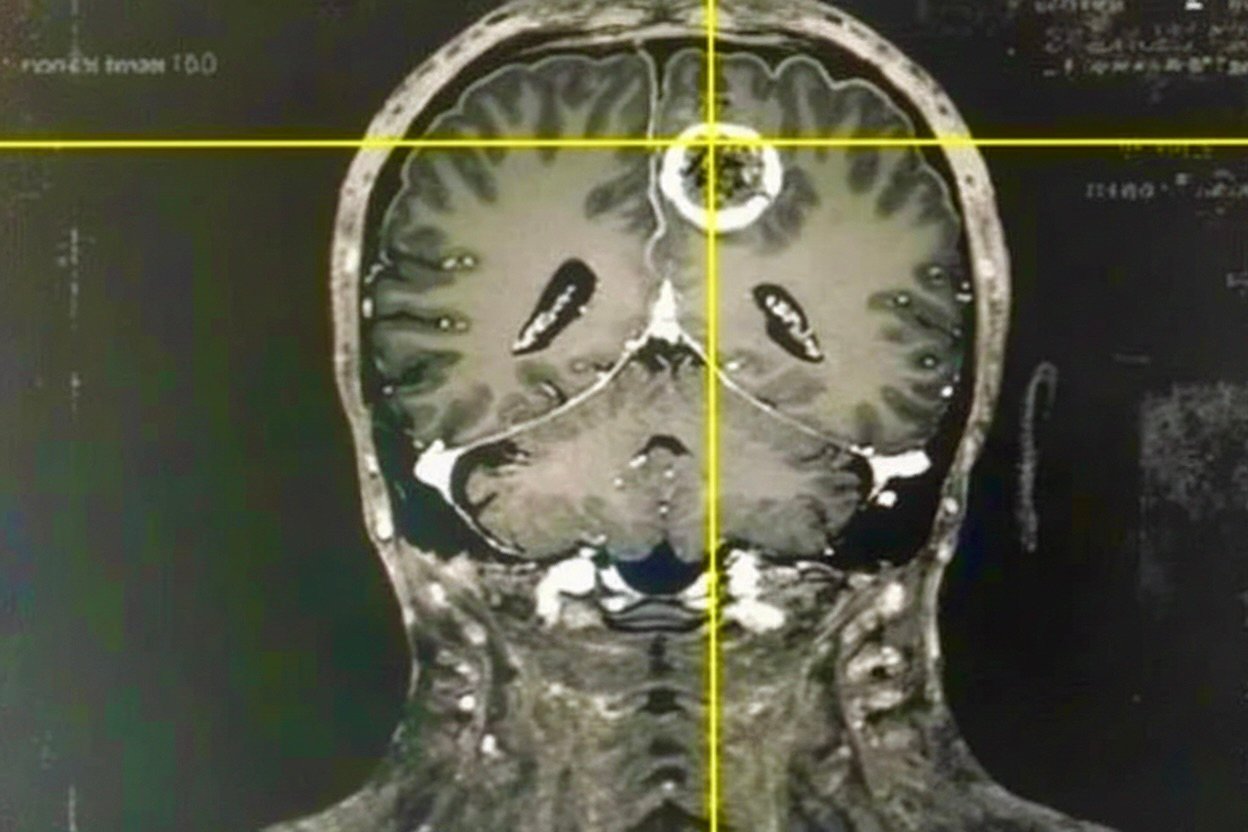

Nézze meg a képet. Egy 39 éves budapesti páciens agyi erei láthatók. Korábban ilyen állapotú ereket csak idősebb korban tapasztaltak, ma viszont sok 40 év feletti embernél előfordulhatnak hasonló problémák. A legnagyobb gond, hogy sokan nem figyelnek az első jelekre, pedig az időben felismert tünetekkel sokat tehetünk egészségünk megőrzéséért.

Agyi érrendszer felvétele — illusztráció

Illusztráció az agyi erek állapotáról — egy 39 éves budapesti páciens agyi ereinek felvétele. A szakértők szerint az ilyen korai jeleket nem szabad figyelmen kívül hagyni — minél hamarabb fordítunk figyelmet az érrendszer egészségére, annál jobbak a hosszú távú kilátások.

40 év felett az erek állapota kiemelt figyelmet igényel. Ha a fenti jelek bármelyikét tartósan tapasztalja, ne halassza el a lépéseket — minél hamarabb foglalkozik az érrendszer egészségével, annál jobbak a kilátások.